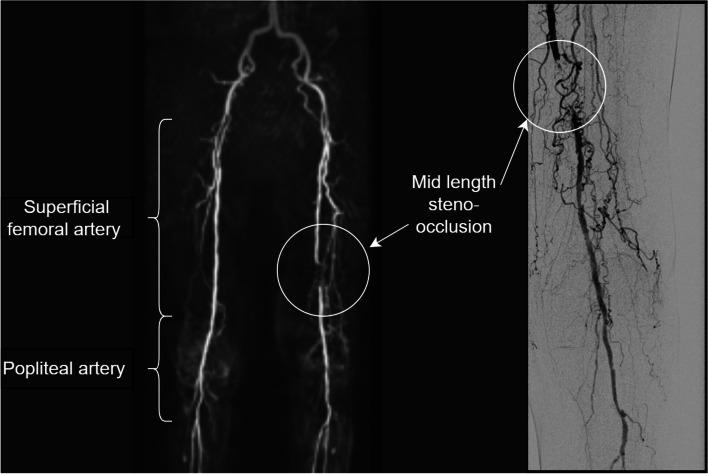

磁共振血管造影检测股腘动脉狭窄闭塞:人工智能的初步经验

Detection of femoropopliteal arterial steno-occlusion at MR angiography: initial experience with artificial intelligence.

This study evaluated a deep learning (DL) algorithm for detecting vessel steno-occlusions in patients with peripheral arterial disease (PAD). It utilised a private dataset, which was acquired and annotated by the authors through their institution and subsequently validated by two blinded readers.

METHODS

A single-centre retrospective study analysed 105 magnetic resonance angiography (MRA) images using an EfficientNet B0 DL model. Initially, inter-reader variability was assessed using the complete dataset. For a subset of these images (29 from the left side and 35 from the right side) where digital subtraction angiography (DSA) data was available as the ground truth, the model's accuracy and the area under the curve at receiver operating characteristics analysis (ROC-AUC) were evaluated.

RESULTS

A total of 105 patient examinations (mean age, 75 years ±12 [mean ± standard deviation], 61 men) were evaluated. Radiologist-DL model agreement had a quadratic weighted Cohen κ ≥ 0.72 (left side) and ≥ 0.66 (right side). Radiologist inter-reader agreement was ≥ 0.90 (left side) and ≥ 0.87 (right side). The DL model achieved a 0.897 accuracy and a 0.913 ROC-AUC (left side) and 0.743 and 0.830 (right side). Radiologists achieved 0.931 and 0.862 accuracies, with 0.930 and 0.861 ROC-AUCs (left side), and 0.800 and 0.799 accuracies, with 0.771 ROC-AUCs (right side).

CONCLUSION

The DL model provided valid results in identifying arterial steno-occlusion in the superficial femoral and popliteal arteries on MRA among PAD patients. However, it did not reach the inter-reader agreement of two radiologists.